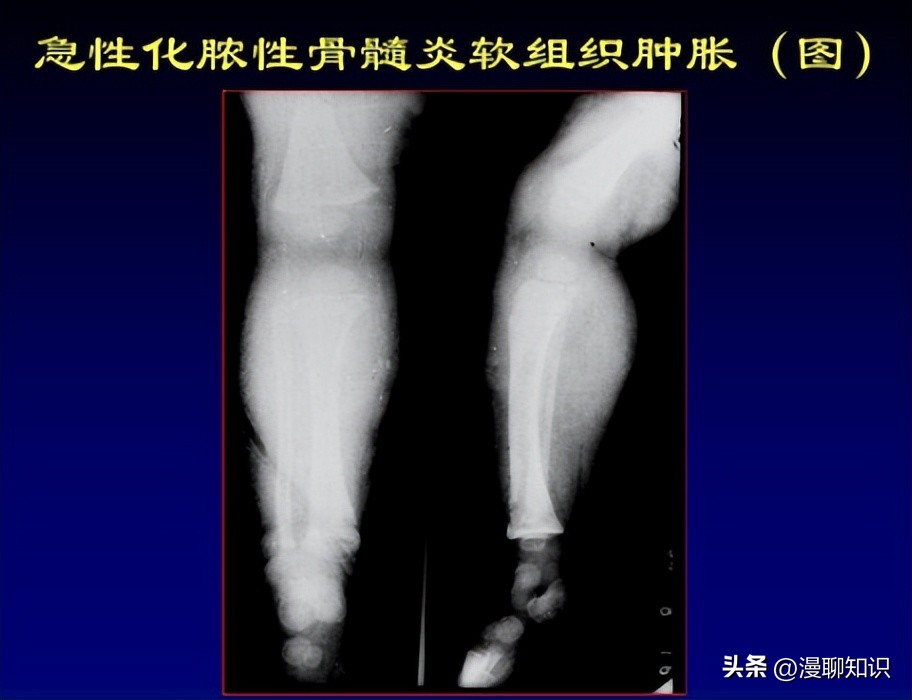

影像学检查呈亚急性或慢性骨髓炎表现,初期X线表现可能正常,之后逐步呈溶骨性和(或)成骨性改变,后期可表现为受累骨骼骨破坏伴边缘硬化。

骨膜反应的程度取决于疾病的持续时间和所涉及的解剖部位。

MRI对疾病早期高度敏感,可在骨破坏和硬化形成之前检测到骨髓水肿,并可评估周围软组织炎症反应。